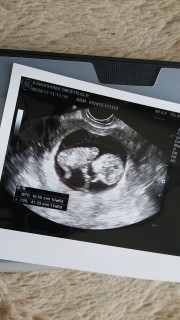

ちょうど、4センチで11wだと言われました。今回はちゃんと手と足があるかを見るだけだよぉ~って、しっかり見えてよかったです!検診にいく度予定日がずれてます…。次は4週間後長いな~。

11w0dで41mmでした。

CRL38.2mm、大横径15mm。

まだまだ子宮内を広々と、手足をバタバタと動かして元気いっぱいでした♪先生にも、大きさもちょうど週数くらいだし順調ですね、と言われ嬉しかったです☆